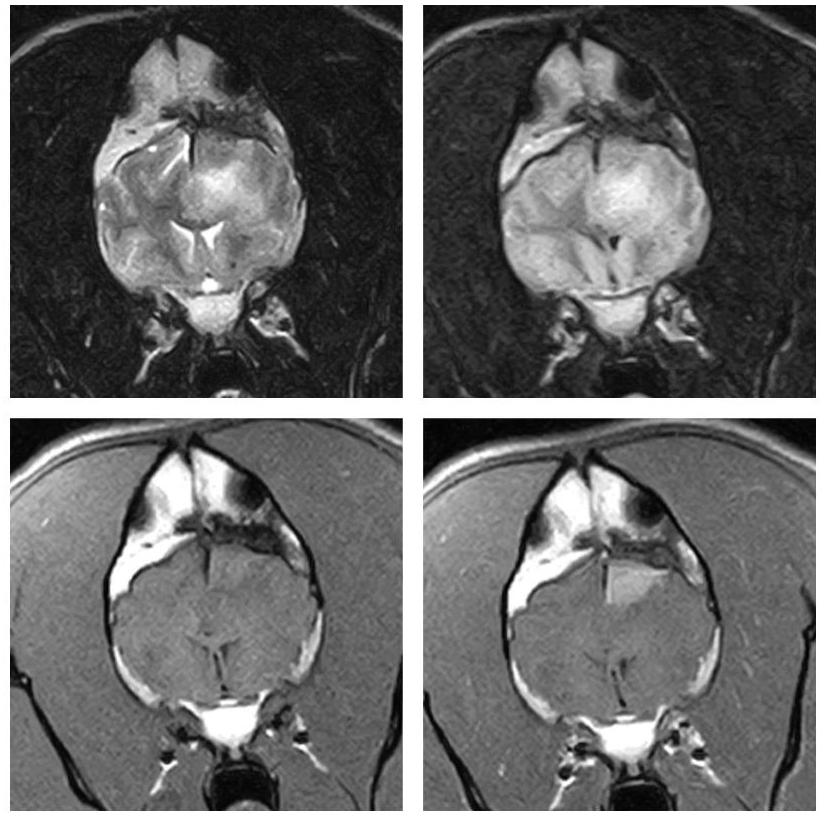

In order to diagnose brain tumours, CT-scans or MRI-scans are used to image the brain. Despite the fact that these tests are very good at detecting the presence of a mass in the brain, they are very poor at identifying its exact nature (i.e. whether it is a tumour, inflammation, or bleeding within the brain).

When it comes to people, a biopsy of a brain tumour is the preferred way to determine the type of tumour and other information regarding treatment and prognosis. Normally, we do not recommend brain biopsy in animals since it is a very invasive and potentially risky procedure. A veterinary neurologist will often diagnose a tumour type based on key features on scans. This approach has limitations, so it is difficult to provide accurate information regarding treatment and prognosis.